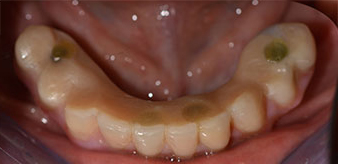

The impression and bite registration were then performed so that the dental technician could begin producing the provisional restoration immediately. This was then screwed in on the same day (Fig. 17 and 18).

Implants